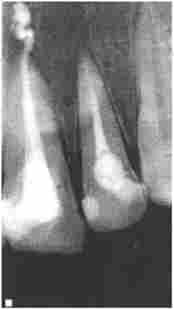

Мал. 10.3. Пацієнт Т., 52 р Контрольна рентгенограма після пломбування зуба 4.5:

послепломбіровочная біль, пломбувальний матеріал визнавств за верхівку кореня